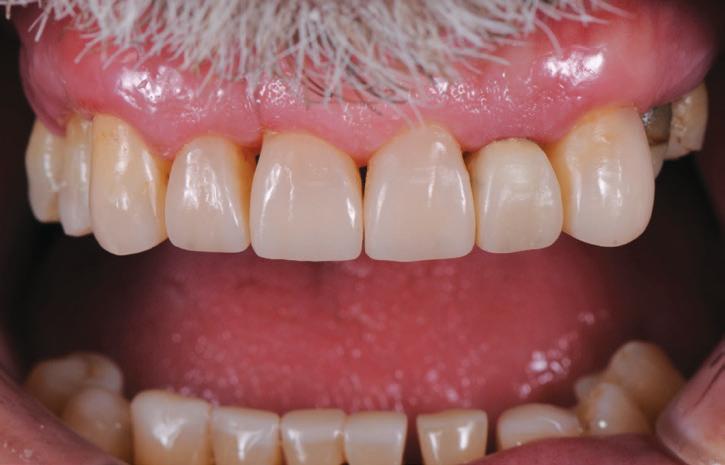

AFTER

Natural colours and a beautiful, life-like surface polish were produced with the multilayered application of this nanocomposite – HarmonizeTM (Fig. 19).

Importantly, the stability of the occlusion was re-established with creation of occlusal contacts on each tooth, and the re-introduction of canine and incisal guidance, to control lateral and protrusive forces (Figs. 20, 21, 22, 23).

Treatment Outcome

The functional and aesthetic results of the treatment are evident in the post-treatment photographs. This gentleman was able to have a full mouth rehabilitation completed in composite resin, achieving the desired improvements in the appearance of his smile, and the return of stability to his dentition, all within a cost that he could afford, by using direct restorative procedures instead of conventional crown and bridgework. This treatment was made